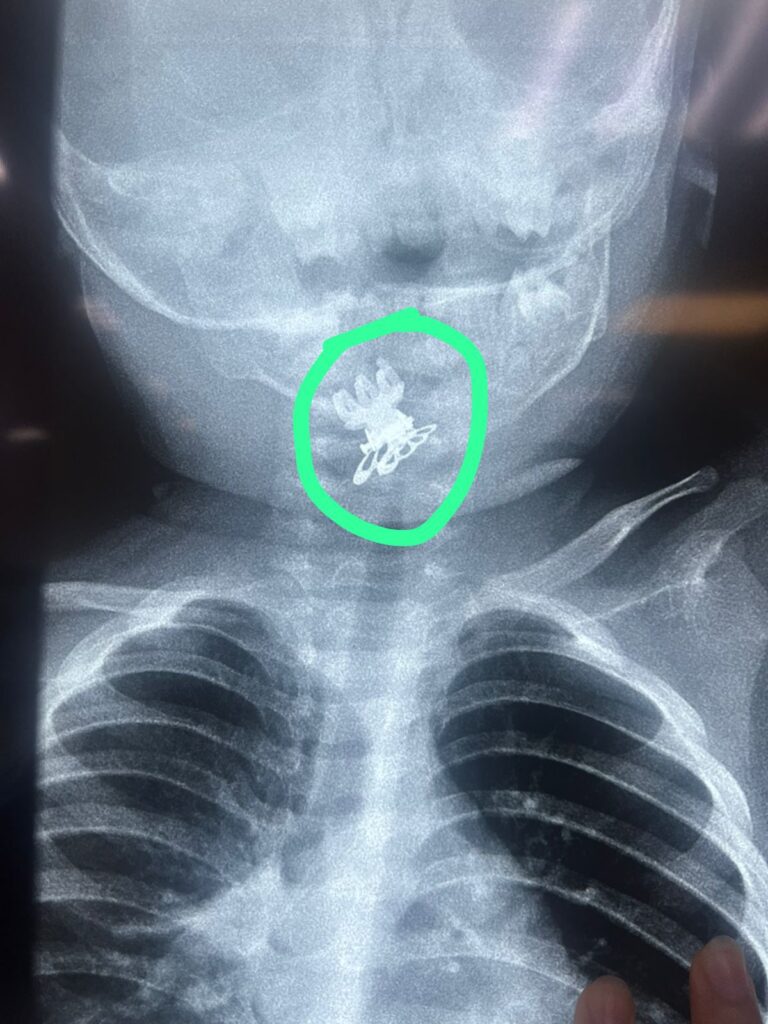

استخراج مشبك شعر (قرّاصه)من مجرى التنفس لطفلة بعمر سنة ونصف في مدينة الصدر الطبية

الاحساء ــ زهير بن جمعة الغزال تمكّن فريق طبي في مدينة الصدر الطبية من إنقاذ